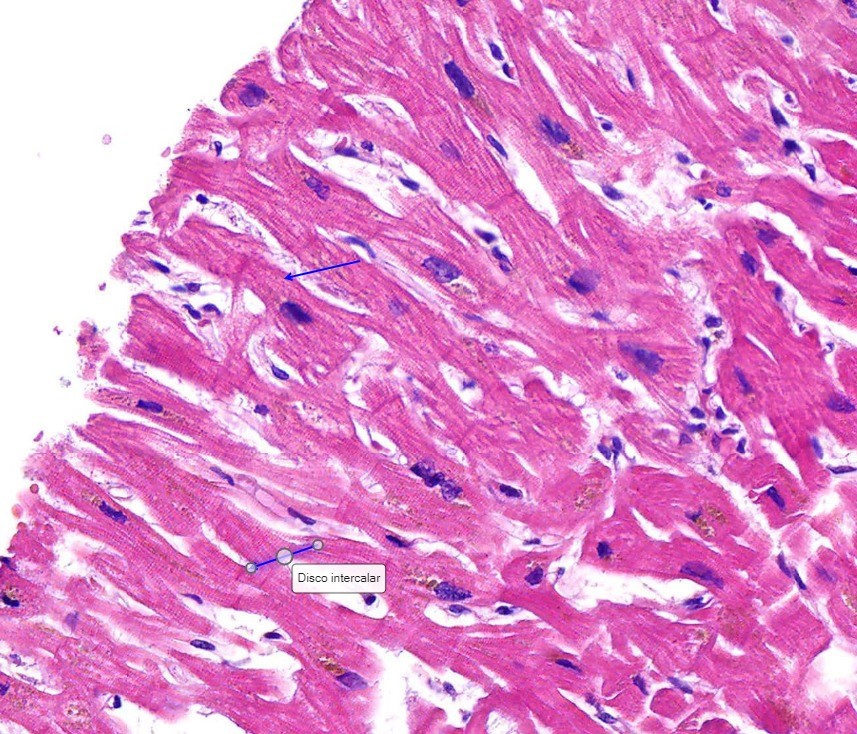

Celula muscular Cardiaca3